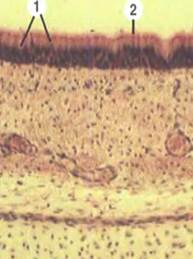

ПРЕПАРАТ № 66 или 177. Однослойный многорядный мерцательный эпителий, прехордального происхождения, защитный. Трахея кролика.

Окраска: гематоксилин-эозин.

При большом увеличении рассмотреть и зарисовать участок эпителия с подлежащей соединительной тканью. Обратить внимание на многорядность эпителия. Ядра клеток расположены на различных уровнях в 2-3 ряда, границы клеток просматриваются плохо вследствие недостаточной разрешающей способности микроскопа. Более четко границы просматриваются у поверхности эпителиального пласта. На апикальной поверхности призматических клеток (ядра их формируют верхний ряд) расположены мерцательные реснички. В сторону базальной мембраны еще просматривается ядра клеток более низких: вставочных, камбиальных и бокаловидных клеток. Бокаловидных клеток в выстилке трахеи мало. Определите бокаловидную клетку со светлой цитоплазмой, так как муцин в процессе гистологической обработки вымывается.

Определить, зарисовать и обозначить: А. Эпителий: 1. Камбиальные клетки. 2. Вставочные клетки. 3. Мерцательные клетки с ресничками. 4. Бокаловидные клетки. Б. Базальная мембрана. В. Соединительная ткань.